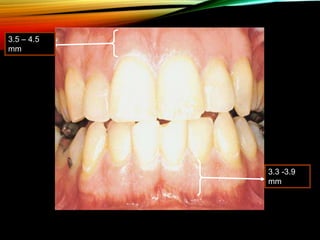

• Width of the attached gingiva

3.5-4.5 mm

3.3-3.9 mm

1st PREMOLAR

1.8 mm

(least)

3.5 – 4.5

mm

3.3 -3.9